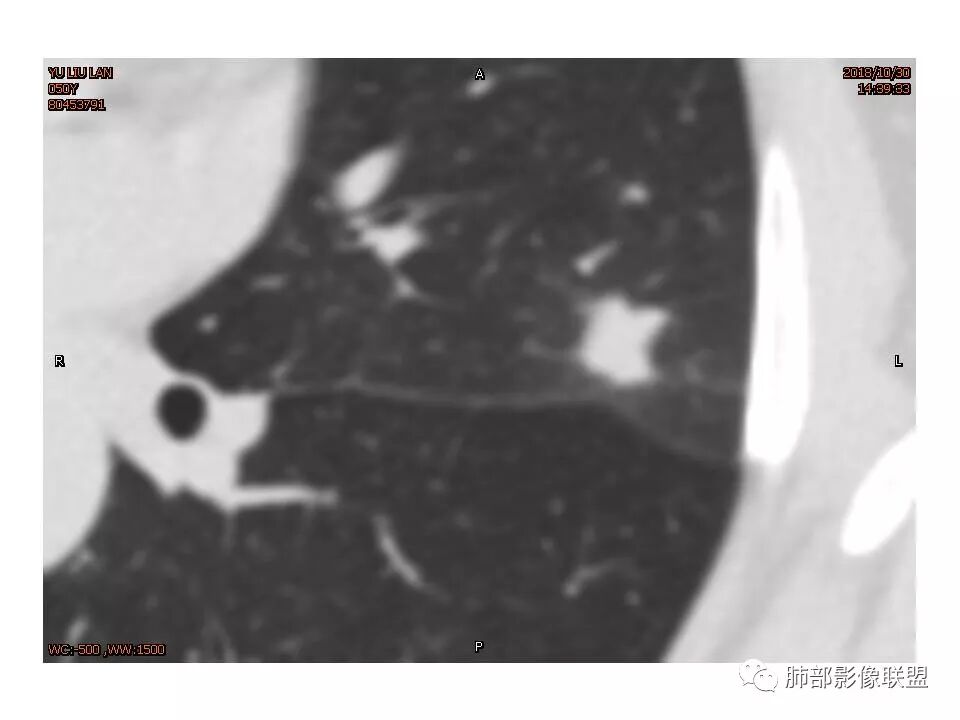

左肺上叶后段病灶,有毛刺,有胸膜牵拉,有血管滋养,好像还可以看见内部空泡,深分叶,边界比较清楚,考虑恶性肿瘤。

左肺上叶实性不规则结节,有深分叶,短毛刺,有切迹,有血管集束,有胸膜牵拉,常规考虑恶性,鉴别炎性结节

女性,左上肺实性结节,有毛刺,有血管进入,边缘彭隆,月牙铲,深分叶,边界比较清楚,胸膜牵拉,考虑腺癌。

左肺上叶结节影,病灶周围呈磨玻璃样改变边缘见毛刺、分叶及胸膜牵拉,增强扫描病灶明显强化,病灶未跨叶间裂,考虑炎性病变,待除外小腺癌。

炎性征象多,平直,长毛刺,尖角征,周围晕模糊,炎性病变放前,腺癌待删,抗炎后复查

结节样病灶,u型征,病灶内可见细支气管管,增强可见血管进入,略增粗,病灶周围有晕,有软毛刺,局部叶间胸膜有牵拉,考虑良性炎性病灶,抗炎后复查。

细小毛刺,梳状平行,周围边缘模糊晕,血管未收侵犯,支气管未见牵拉扩张,多条淋巴道与胸膜相联,倾向于炎性病变

左上肺实性结节,有血管集束、分叶、棘突、胸膜牵拉、长毛刺为主,周围有晕边界不清,有恶性征象但还是感觉炎性(PC?)可能大

1.胸膜下略不规则实性密度结节影,孤立,缺乏典型深分叶,可见淡薄边界模糊磨玻璃晕,可见相对细长软毛刺。

2.如南边老师分析,病灶缺乏边缘膨隆优势,甚至部分平直内收。

3.病灶收缩力不强,整体强化程度不显著。

4.综上,病灶更符合炎性,如隐球菌感染等,而不大符合肺腺癌。具体到机化性肺炎略有些出乎预料。